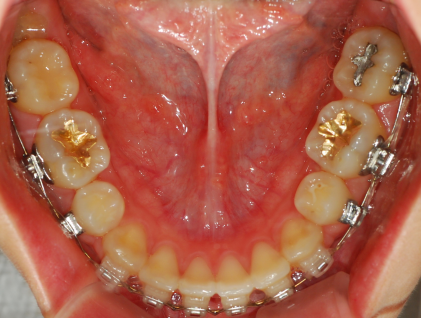

하악사진